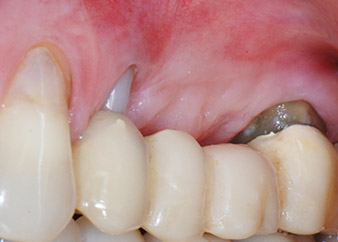

Einen Monat nach dem Eingriff waren sowohl die Schmerzen als auch die Entzündung an Zahn 24 minimal, die Zahnbeweglichkeit lag jedoch noch bei Miller-Klasse 2. Nach Freilegung und Reinigen des infizierten periapikalen und periradikulären Gewebes wurde das Ausmaß des Knochendefizits deutlich (Abb. 2 und 3).

An der bukkalen Wurzel fehlte der gesamte vestibuläre und distale Knochen. Das Attachment beschränkte sich weitgehend auf die palatinale Wurzel, was die anfängliche schlechte Prognose unterstreicht. Auch Zahn 27 wies ein verringertes horizontales Attachment (vgl. Abb. 12) und eine kleine apikale Aufhellung (Abb. 1) auf, allerdings ohne klinische Symptome.